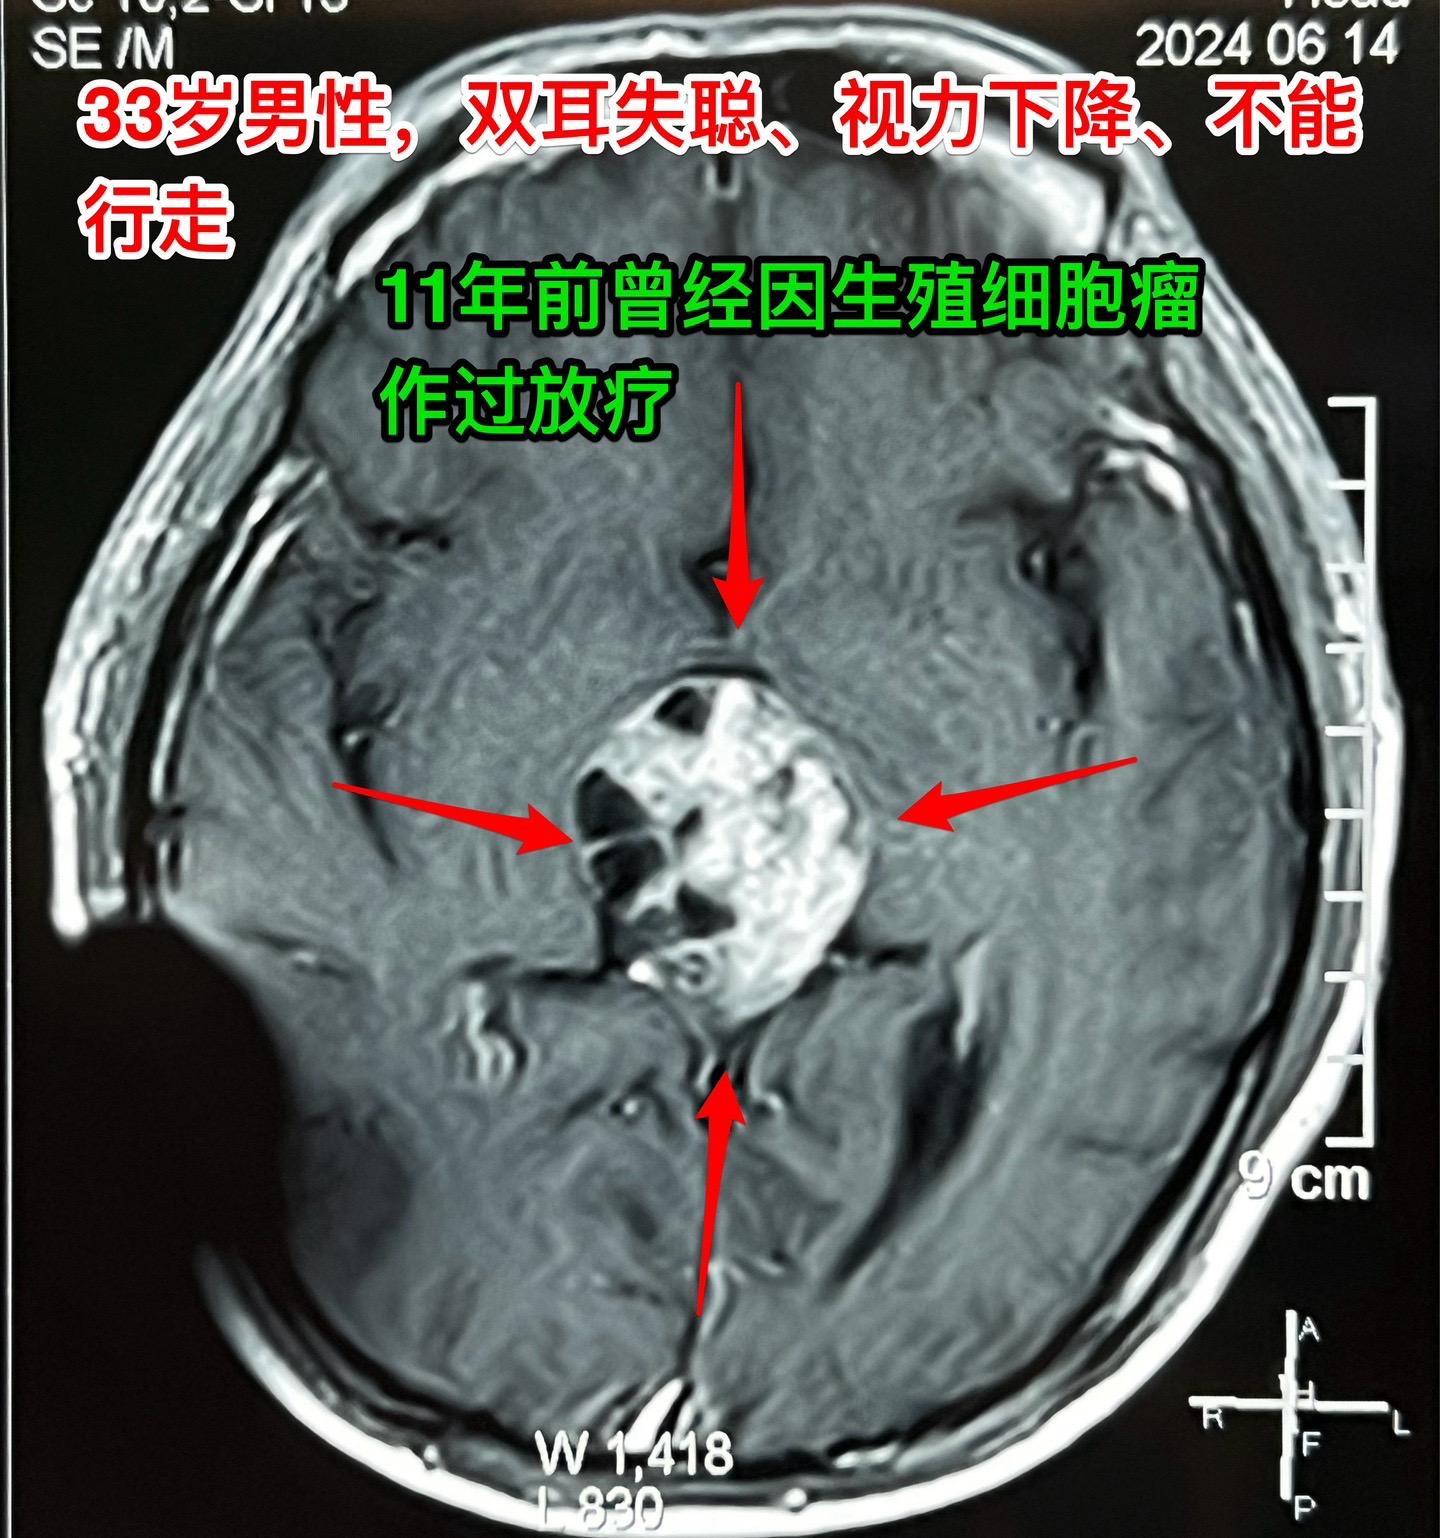

33岁贵州男性,脑部畸胎瘤。33岁贵州男性,病史11年。 11年前因多饮多尿在北京市某医院按生殖细胞瘤行全脑放疗,之后症状好转,能工作。 近两个月他记忆力差、爱睡觉、听力下降、视力下降。脑部磁共振显示松果体区肿瘤,在北京市某医院行肿瘤穿刺活检术,病理报告结果考虑是乳头型颅咽管瘤(活检标本标注为鞍区占位,可能误导了病理科医生,见图6)。 放疗医生及化疗医生说根据这个病理 结果是不敢实施放疗和化疗的。神经外科医生说开颅切除肿瘤风险非常大。 处于绝